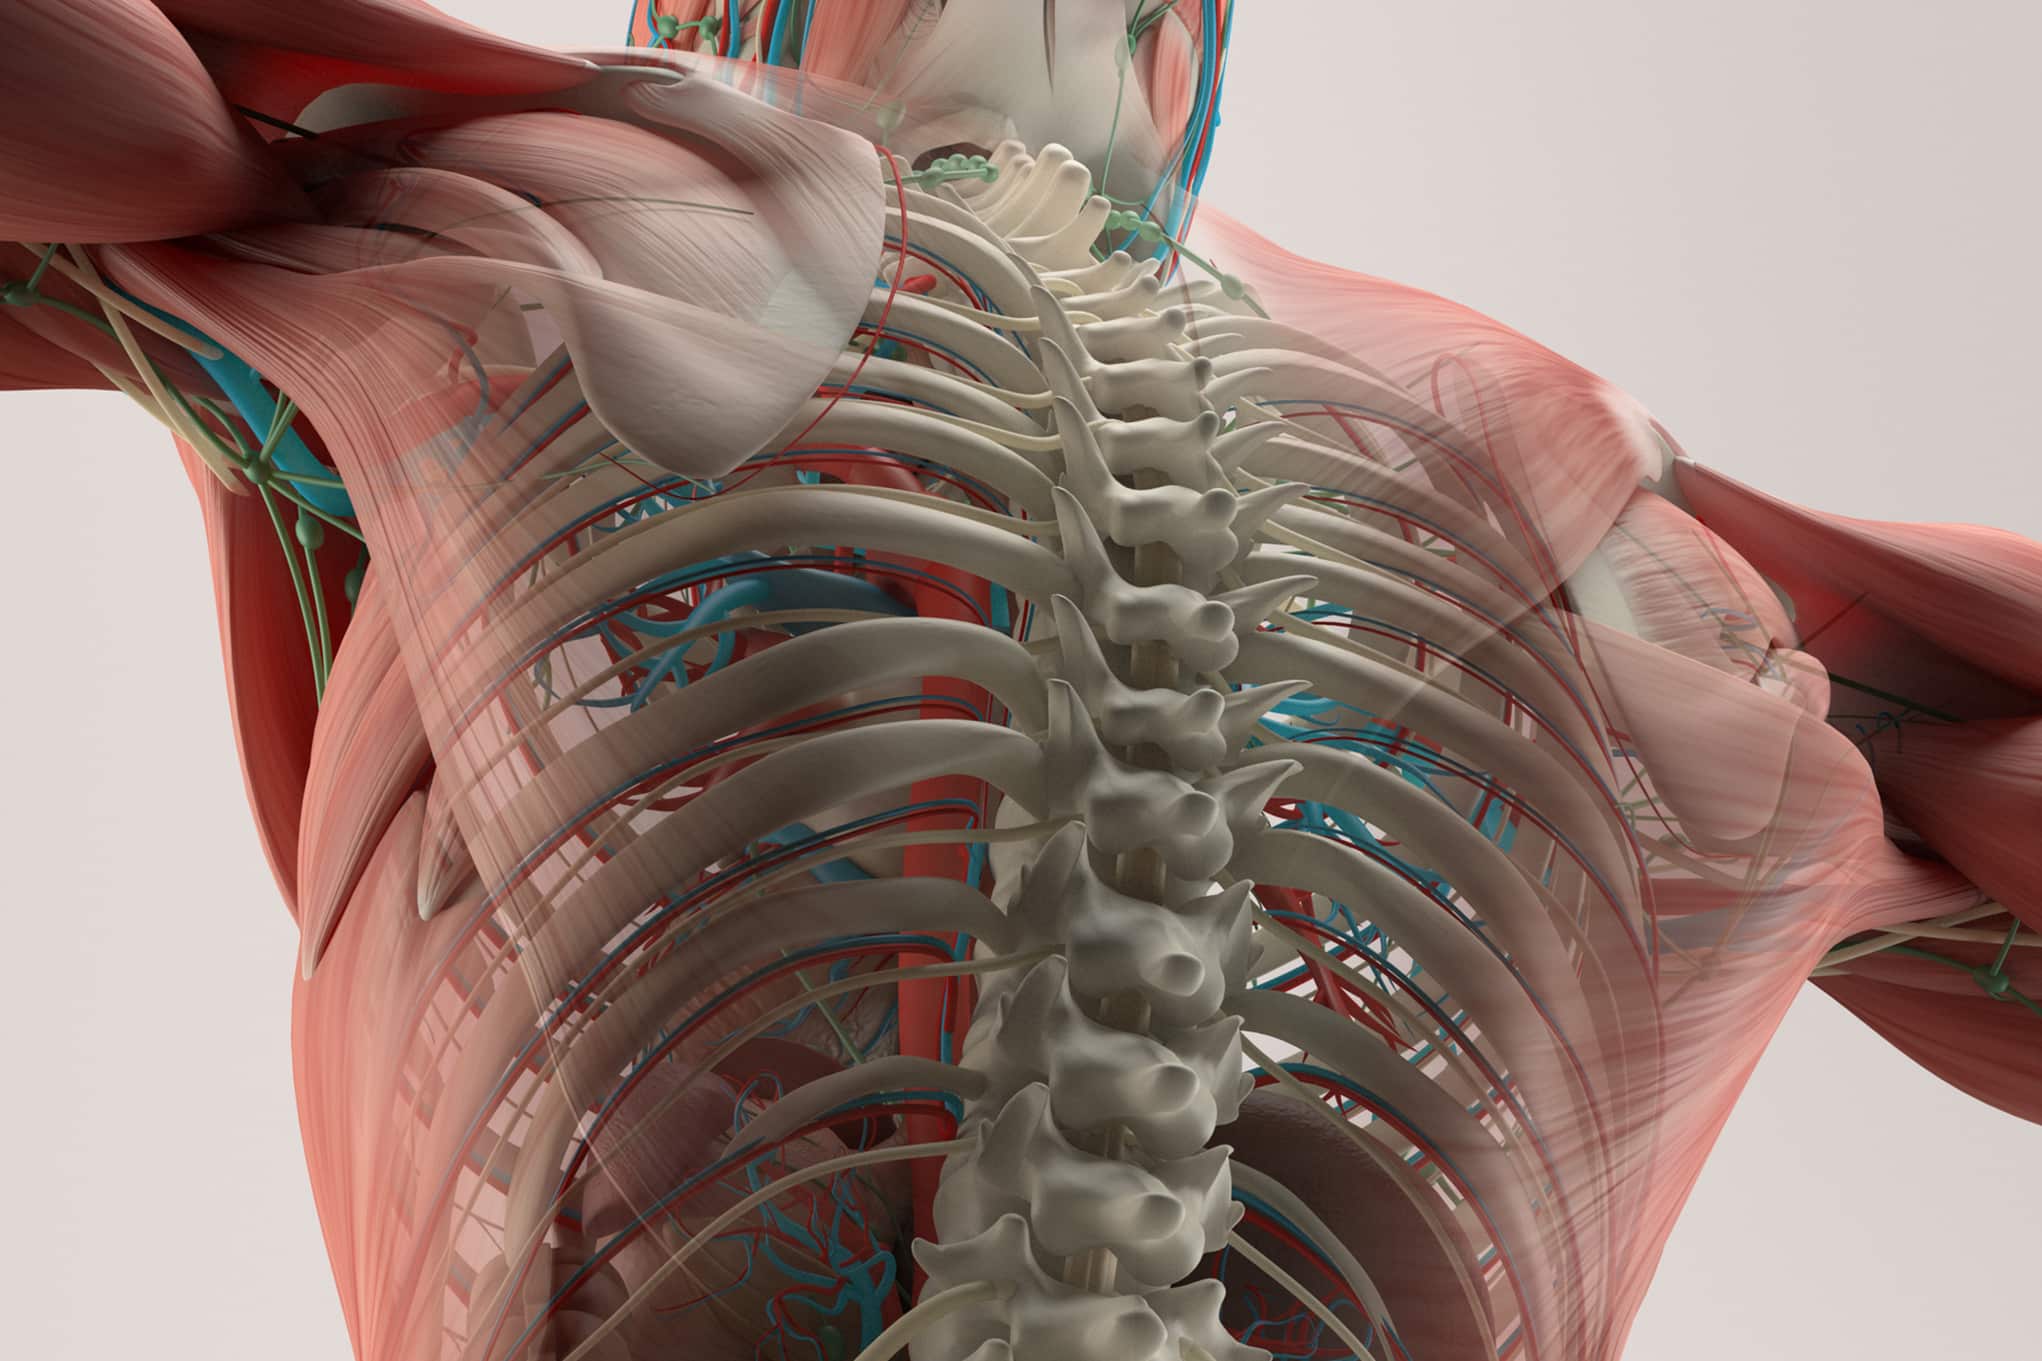

Allows students to visualize realistic human anatomy with 3D models.

The captivating detail of 3D anatomical models are perfect for helping students visualize things that would otherwise be impossible for them to see. They can zoom in and rotate AR-enhanced 3D anatomical models, literally at their fingertips. Check back often – we’ll be adding more 3D models in the coming months that students will want to explore.